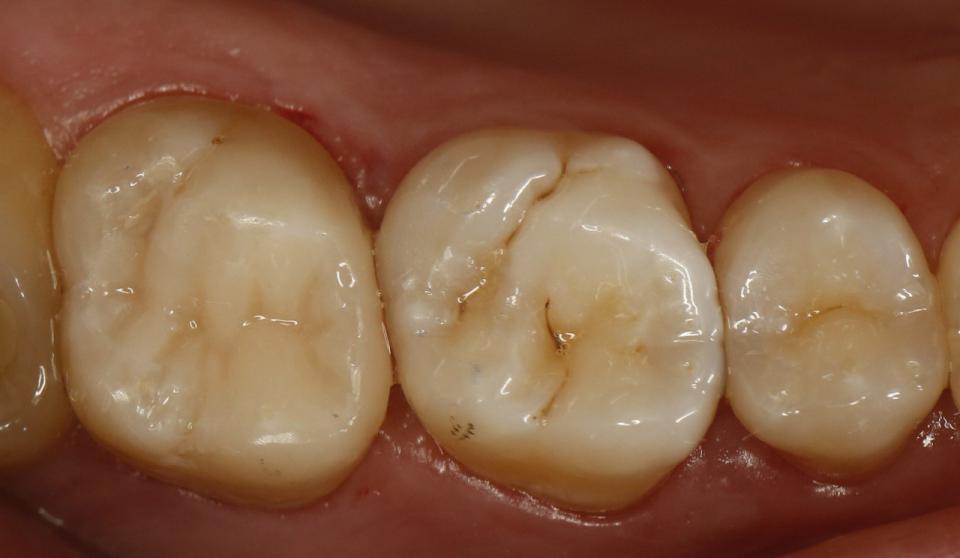

paraschyk1 Опубликовано 16 октября, 2015 Автор Опубликовано 16 октября, 2015 Это где ставят по 200гр?))бор нормальный стоит только гривен 40,а еще сам материал,полиры,паста полировочная,протравка,бонд, ершики для бонда,матрицца и матрицадержатель,анестетик,иголки доя карпульного шприца, ретракционная нить.Пачка перчаток 50 пар уже за 150гр перевалила,салфетки. А еще переодически новые наконечники надо покупать...Антисептики для рук и инструмента стоят дохера..А еще долгосрочные-амортизация ремонт установки, новые инструменты(пакеры,гладилки,зеркала...)А еще аренда(платный план) на который тоже идет свой материал(от 10 ки)... Вижу в теме. Ты забыл время. Время самое ценное. А пакеры и ершики копейки. Увы,но в Киеве еще можно поставить пломбы аля лепнина,за 200 грн. Но и срок им мал и вид соответствующий Но вот такую работу делать за 200грн я не буду,ну разве корешу.

paraschyk1 Опубликовано 16 октября, 2015 Автор Опубликовано 16 октября, 2015 Выпал недавно реставрированный жевательный семерка вместе со штифтами. Т.е. там остались одни корни, над десной ничего от зуба нет. Было 2 штифта, реставрация + обычная простая коронка сверху. Все это аккуратно выпало. Один стоматолог говорит, что даже браться не будет, мол через годик снова отвалится, только вырывать. Другой говорит, что здоровый корень, какой нафиг рвать, только делать. Ниже вариант спасения зуба,когда полная жопа. Такой зуб может бегать пять лет и более.